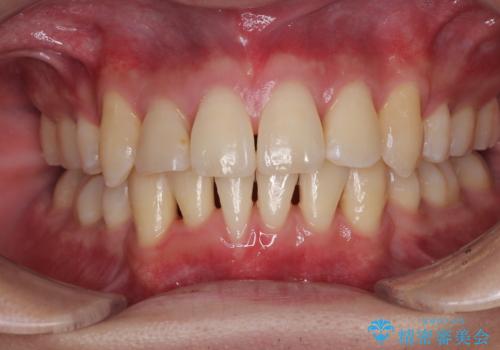

前歯のデコボコをインビザラインで目立たずに改善